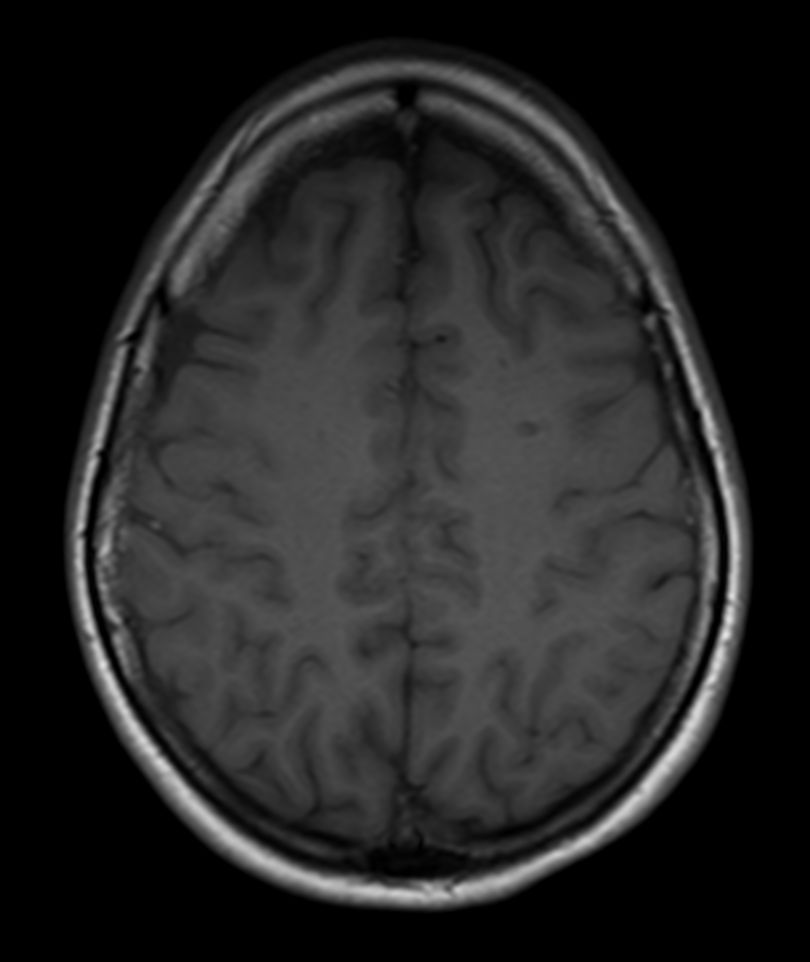

SWI sequence has a high sensitivity to enhance contrast for deoxygenated (venous) blood or calcium deposits. This may help, when used in combination with other clinical information, in the diagnosis of various neurological pathologies. 3D imaging lets you acquire high resolution data in multiple directions in one scan. Isotropic voxel size enables reformats in any plane without loss of resolution. FLAIR* requires offline post processing combining the contrast of 3D FLAIR and 3D SWI EPI into a single image. This enables the visualization of Central Vein Sign, mapping subcortical veins onto 3D FLAIR contrast images.